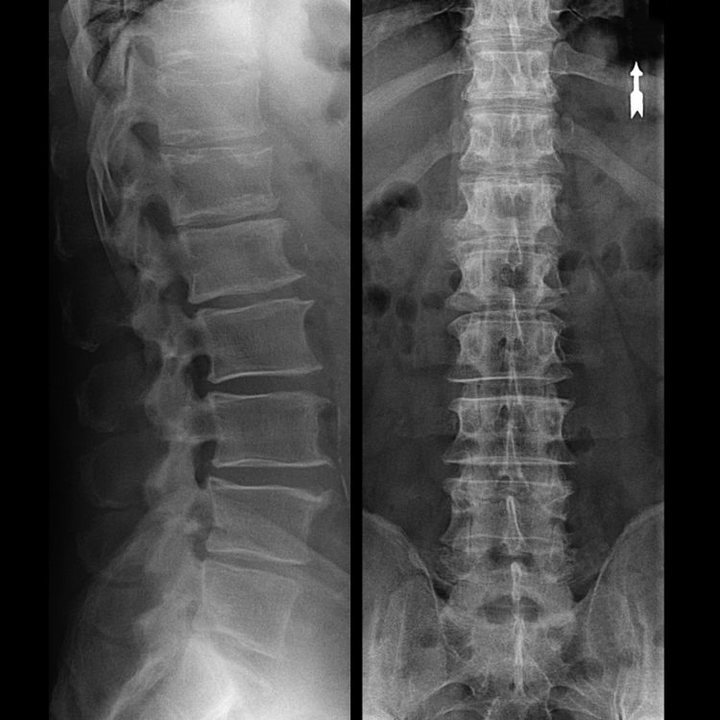

Unha "radiografía" da columna cervical e mesmo as probas funcionais de flexión e extensión non mostran cartilaxe porque o seu tecido permite o paso dos raios X. Non obstante, en función da localización das vértebras, pódense extraer conclusións xerais sobre a altura dos discos intervertebrais, o endereitamento xeral da curvatura fisiolóxica do pescozo - lordose - así como a presenza de crecementos marxinais nas vértebras con irritación prolongada das súas superficies por discos intervertebrais fráxiles e deshidratados. As probas funcionais poden confirmar o diagnóstico de inestabilidade da columna cervical.

Dado que os propios discos intervertebrais só son visibles mediante TC ou resonancia magnética, a resonancia magnética e a tomografía computarizada de raios X están indicadas para aclarar a estrutura interna da cartilaxe e formacións como protuberancias e hernias. Así, coa axuda destes métodos, faise un diagnóstico preciso e o resultado da tomografía é unha indicación e mesmo unha guía real para o tratamento cirúrxico dunha hernia inguinal no departamento de neurocirurxía.